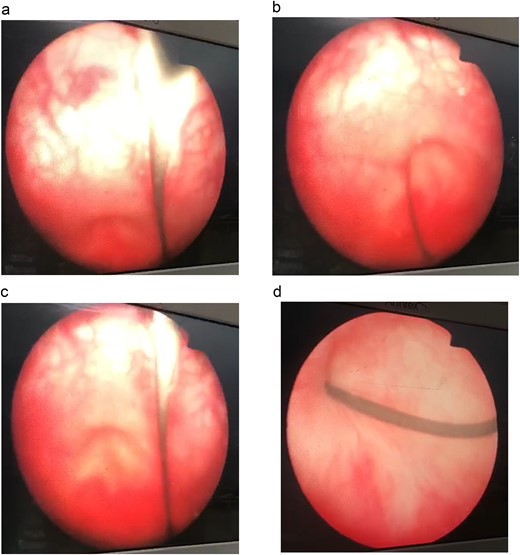

Antegrade and retrograde cystoscopy revealed a damaged urethra and cystitis (Fig. 1). The cystoscope passed smoothly through the suprapubic site, though it was difficult to navigate the urethra.